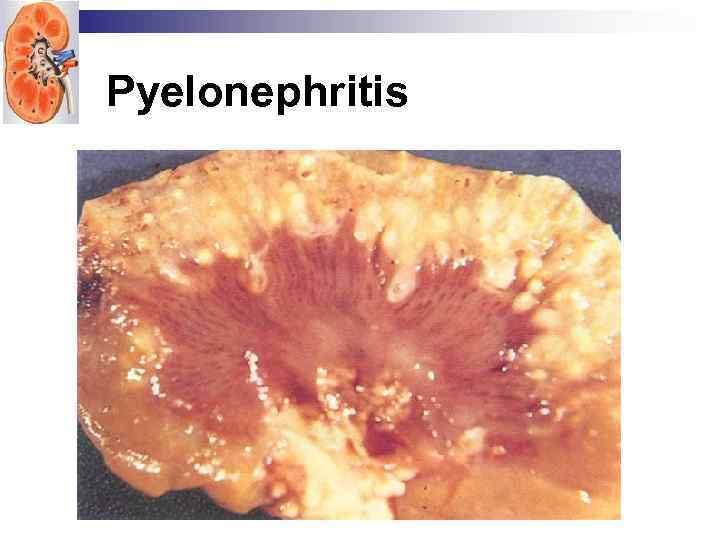

Pyelonephritis

Pyelonephritis